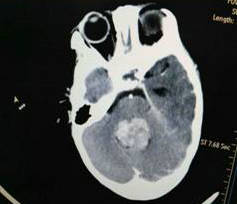

近日,郑州大学五附院神经外科二病区收治了一名因第四脑室肿瘤引起急性脑积水1岁患儿,入院时表现为频繁呕吐、精神萎靡,神经外科二病区吴建珩副主任医师带领的诊疗组接诊后考虑患儿为肿瘤堵塞脑脊液循环通路,造成梗阻性脑积水及颅内压增高,时间就是生命,来不及常规行MRI检查,急诊行增强CT检查,CT检查结果回示患者小脑蚓部巨大肿瘤充满第四脑室,大小约30mm×30mm×35mm,考虑室管膜瘤,脑积水严重,脑疝风险极高,生命危在旦夕。患儿才刚满1岁不久,正是父母的心头的宝,若是遭此不幸,毫无疑问对其父母以及整个家庭都是难以承受的巨大的打击。

术前:肿瘤组织巨大